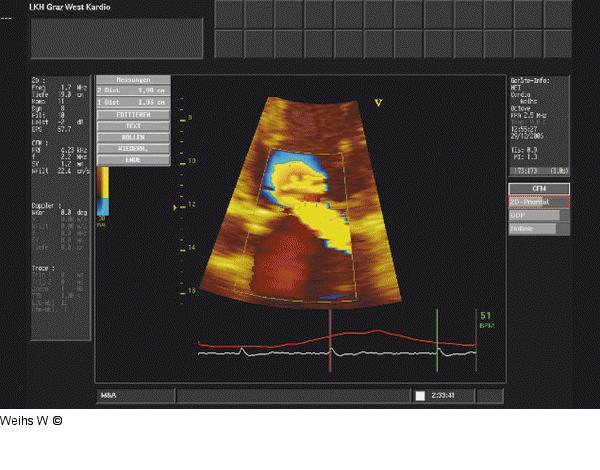

Abbildung 7: Echo Darstellung der PISA. Der Radius beträgt > 1 cm², die Vena contracta misst 1,0 cm. Es errechnet sich ein Regurgitationsvolumen von 70 ml. |

Abbildung 7: Echo

Darstellung der PISA. Der Radius beträgt > 1 cm², die Vena contracta misst 1,0 cm. Es errechnet sich ein Regurgitationsvolumen von 70 ml. |